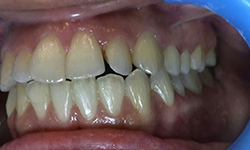

(9) Metal Ceramic Crowns

Before Treatment

After Treatment

Mr. Shiv Narayan Singh,aged 78yrs, came with a concern of multiple broken and mobile teeth with difficulty in chewing food. So, multiple RCTs followed by metal-ceramic crowns were delivered to the patient ,restoring his beautiful smile.